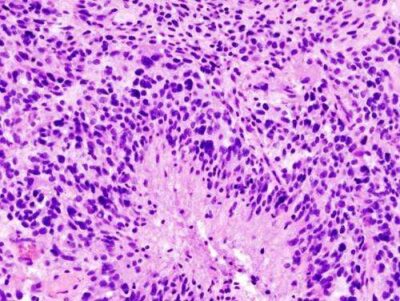

Glioblastoma-Immagine:Glioblastoma (diapositiva istologica). Credito: Wikipedia/CC BY-SA 3.0-